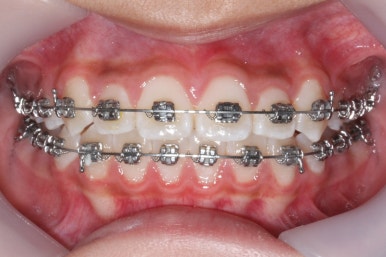

장치를 부착한 후에 순차적으로 변화가 나타나는 모습입니다.

총 4장의 사진 동안 경과한 시간은 불과 6개월 입니다. 헤드기어를 통해 사전에 작업을 해뒀기 때문에 이후 연산동덧니교정 과정은 편해진 것이죠.

윗니만 6개월이 지난 모습입니다.

치열이 매우 가지런해졌죠. 이 후에는 특이사항 없이 종료가 되었습니다.

미소를 짓거나 웃는 모습이 확연히 좋아졌습니다.

덧니가 없어져서 그런지 입술 다문 모습도 편안함이 느껴지네요. 턱끝의 쭈글한 주름도 없어졌습니다.

헤드기어를 사용해서 옆모습의 돌출감도 개선이 되었고 무턱같아 보이던 외모도 많이 좋아졌네요.

이 정도면 비발치 연산동덧니교정으로도 충분히 좋았던 효과를 보았습니다.

연산동덧니교정을 하고자 키다리아저씨치과에 처음 내원했을 때와 개선이 된 후의 비교 모습입니다. 영구치가 모두 나왔고 덧니가 개선이 된 후에 마무리가 되었습니다.

처음에 언급했듯이 헤드기어에서 부터 장치부착까지 총 교정 기간은 1년 8개월이였습니ㅏㄷ.